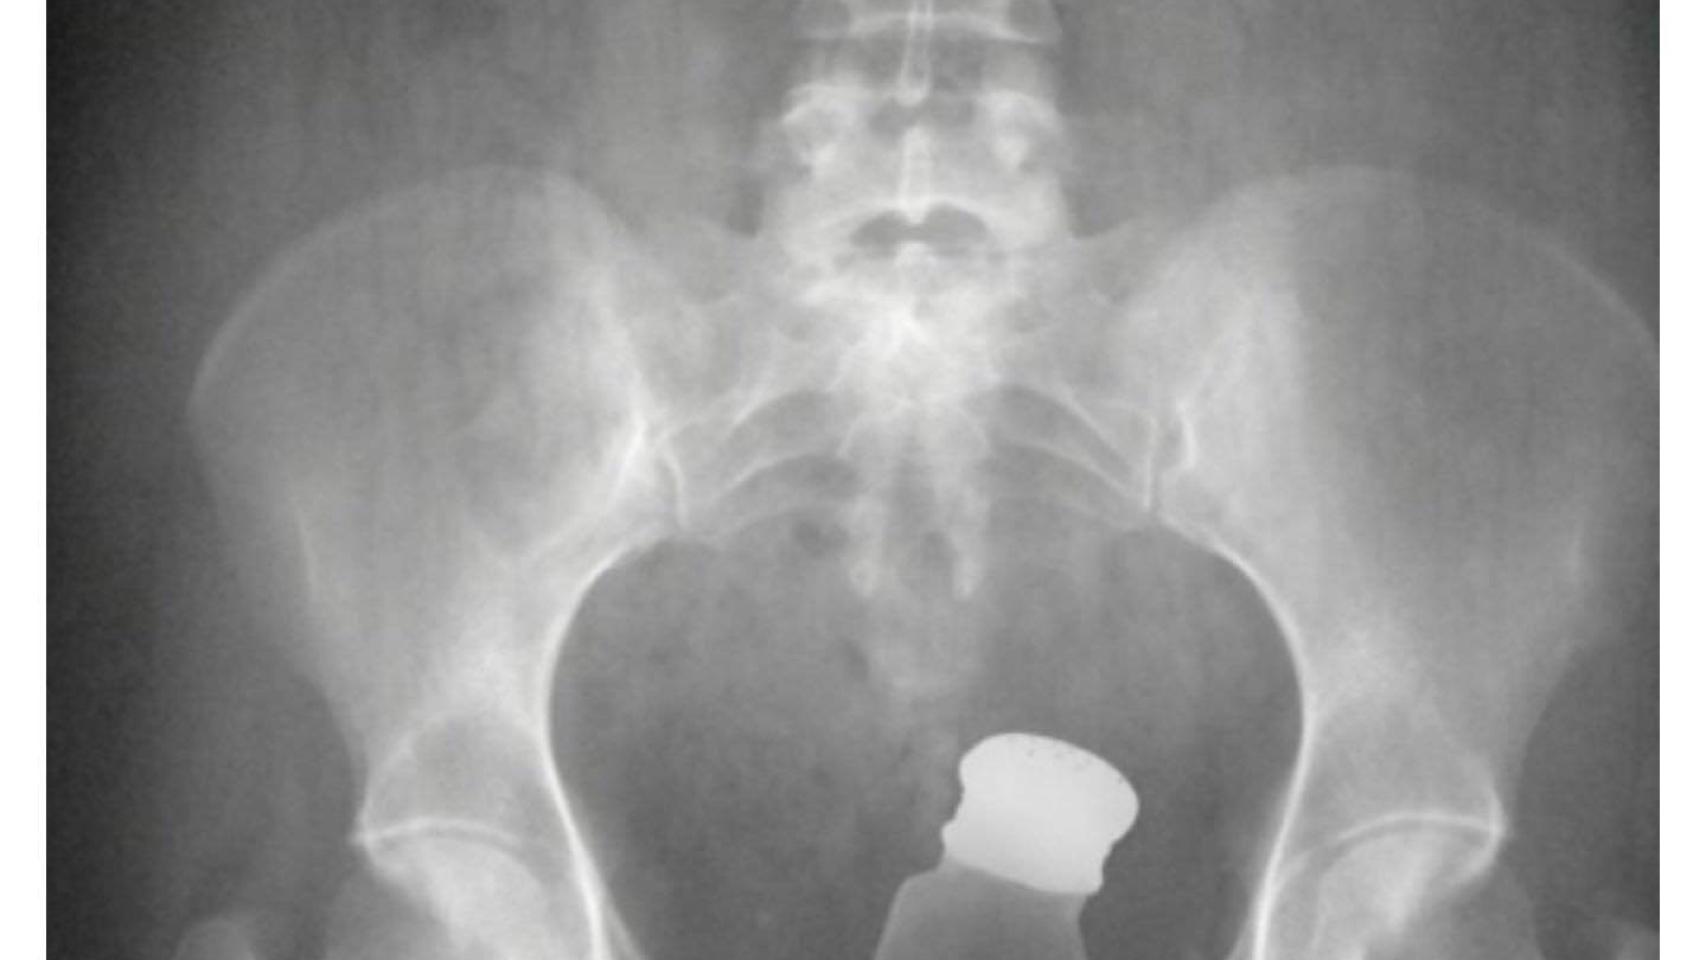

La radiografía muestra que el recluso ingirió droga para introducirla en prisión